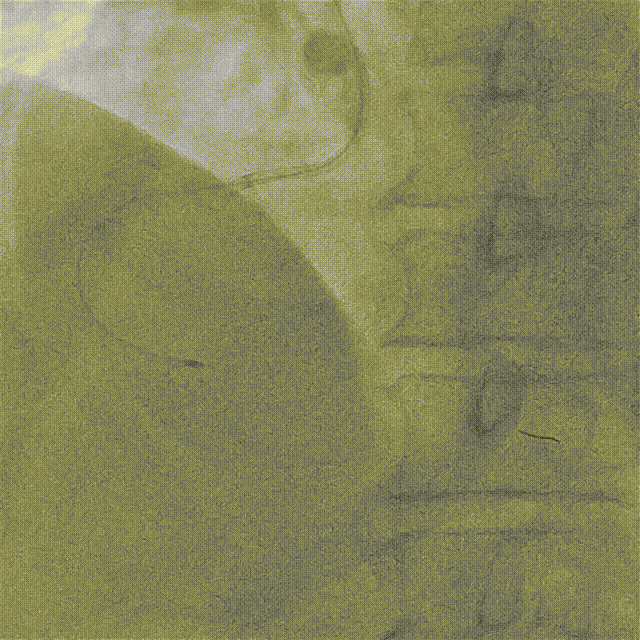

ROTA 1.5Burr首次旋磨

1.5mm旋磨头分段式旋磨RCA近、中、远段病变,轻进快退“啄米式”充分旋磨近端后再逐步前进,旋磨头顺利通过近中段病变并对病变处进行充分打磨。

1.5mm旋磨头通过中远段病变,对钙化病变充分进行旋磨抛光。